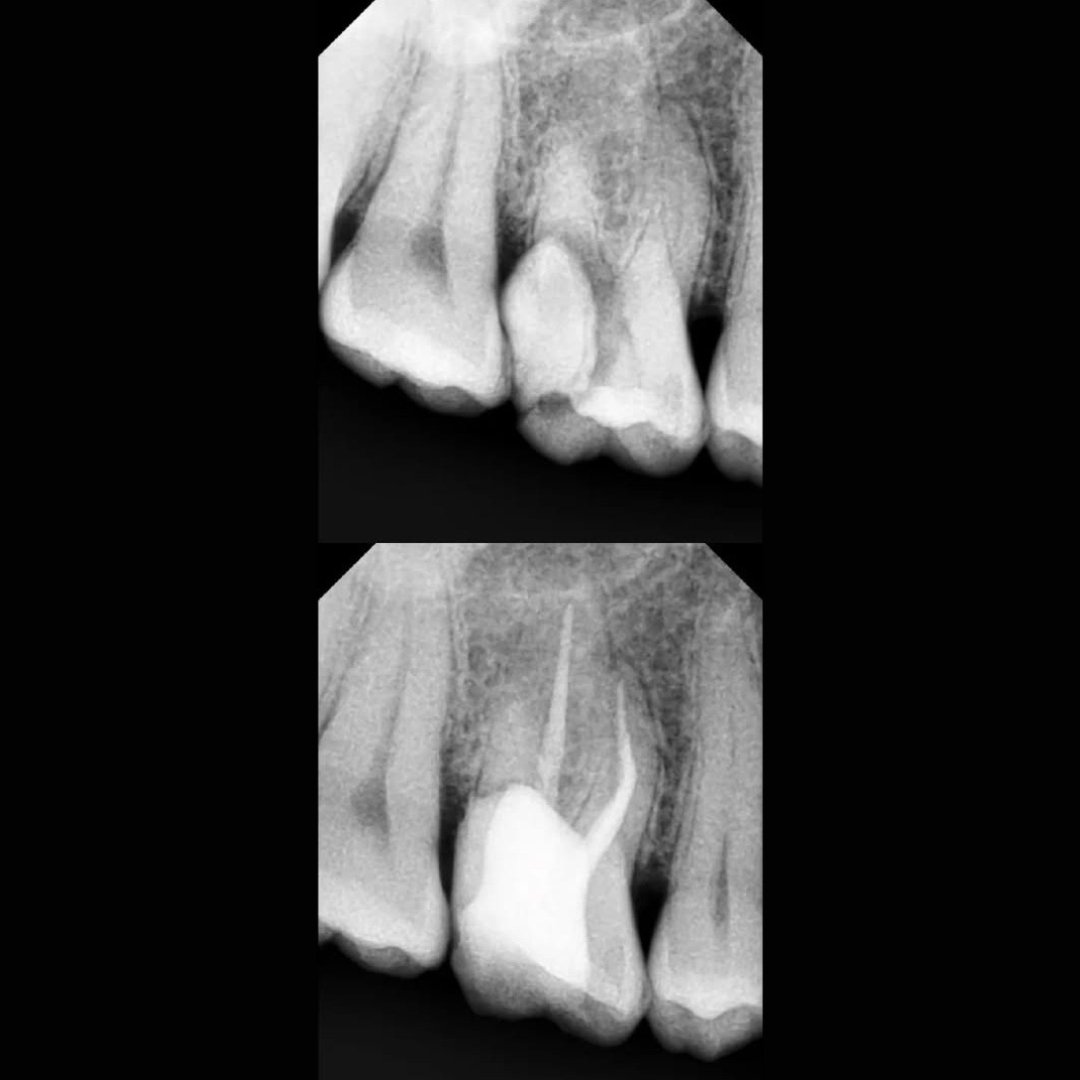

Before After Perawatan Saluran Akar (PSA) di Klinik Utama Pondok Gigi Jakarta

Transformasi nyata setelah perawatan saluran akar (PSA) di Klinik Utama Pondok Gigi Jakarta. Dari gigi rusak dan nyeri hingga kembali sehat dan berfungsi normal. Dikerjakan oleh dokter gigi profesional dengan teknik endodontik modern dan alat berteknologi tinggi untuk hasil maksimal.